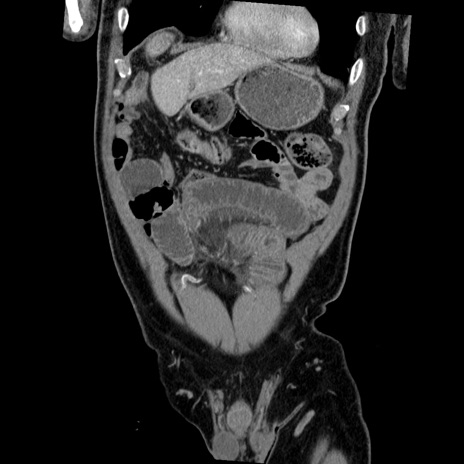

症例22(冠状断像)

【症例】50歳代男性

【主訴】腹痛

【現病歴】AVMからの被殻出血のため回復期リハ病棟入院中。 本日午後3時頃急に下腹部痛が出現した。

【既往歴】AVM、被殻出血、虫垂炎、高血圧

【身体所見】意識晴明、左半身不全麻痺、会話の理解は良好、36.5°C、腹部:膨隆、全体に板状硬、下腹部正中に圧痛点あり、反跳痛-、筋性防御不明、右下腹部にope scar

【データ】WBC 9400、CRP 0.06